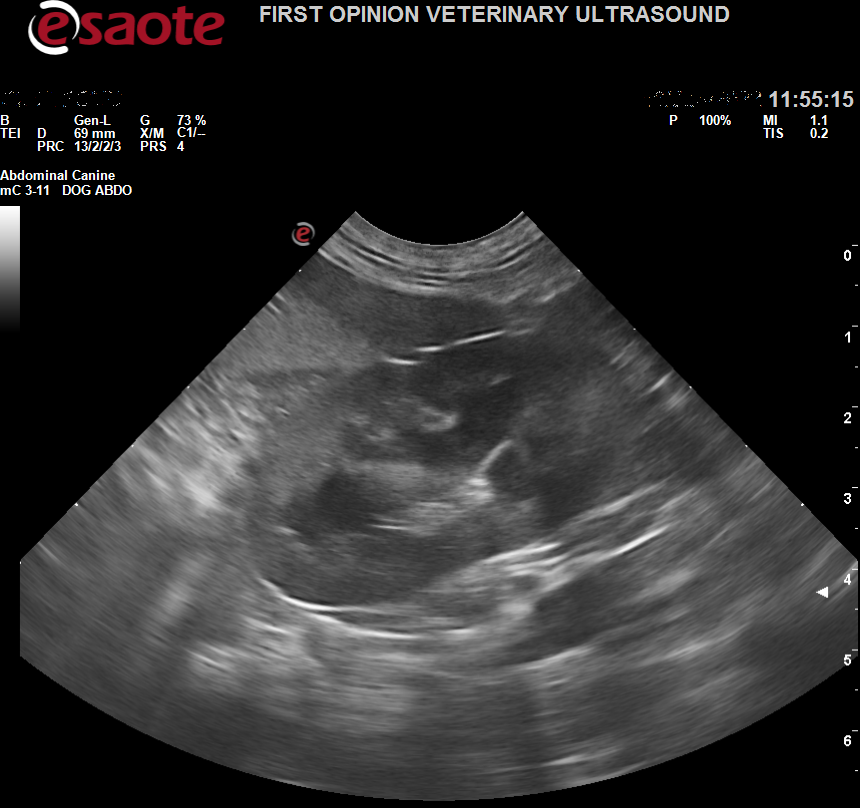

The Esaote MyLab Omega is a step up from the Sigma model. It is a portable version of the cart based machine X7. I was blown away by this machine. The Omega has immense image quality.

They have also introduced a preset that highlights gastrointestinal tract walls brilliantly and in great detail. The image quality is just outstanding, and it certainly is a step up from the Sigma and X5 models in image quality.

Images from the Omega